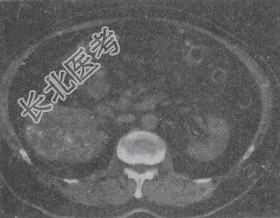

- 单项选择题患者,男, 51岁。右肾区不适4个月余,有镜下血尿。CT扫描结果见图。最有可能的诊断是

A、肾癌

B、肾盂癌

C、肾错构瘤

D、肾结核

E、肾腺瘤